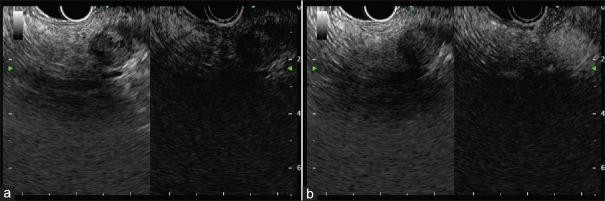

Contrast harmonic endoscopic ultrasonography (CH-EUS) is a new technique which allows the dynamic study of the microvascularization of a target tissue. Its application is validated for the diagnosis of pancreatic adenocarcinoma but remains unclear for other solid pancreatic tumors (neuroendocrine tumors [NETs], autoimmune pancreatitis [AIP], metastases). The purpose of this review is to outline the potential role of the CH-EUS in these indications. NETs are typically iso/hyperenhanced at CH-EUS, and a heterogeneous enhancement seems a good predictor of malignancy in neuroendocrine pancreatic tumor. AIP is often iso/hyperenhanced at CH-EUS. Quantitative analysis of time-intensity parameters is promising for the distinction between pancreatic adenocarcinoma and AIP. The appearance of pancreatic metastases at CH-EUS is various depending on the origin of the primary tumor. Data from the literature remain to this day weak to determine the role of the CH-EUS in the management of rare solid tumor of the pancreas (NETs, AIP, and metastases). Specific studies are expected to further clarify the impact of this procedure in this field.

对比谐波内镜超声检查(CH-EUS)是一种可对目标组织微血管化进行动态研究的新技术。其在胰腺腺癌诊断中的应用已得到验证,但在其他胰腺实性肿瘤(神经内分泌肿瘤[NETs]、自身免疫性胰腺炎[AIP]、转移瘤)中的应用仍不明确。本综述的目的是概述CH-EUS在这些适应症中的潜在作用。NETs在CH-EUS检查时通常表现为等增强/高增强,而异质性增强似乎是胰腺神经内分泌肿瘤恶性程度的良好预测指标。AIP在CH-EUS检查时通常也表现为等增强/高增强。时间-强度参数的定量分析有望用于区分胰腺腺癌和AIP。CH-EUS检查时胰腺转移瘤的表现因原发肿瘤的来源而异。时至今日,文献数据仍不足以确定CH-EUS在胰腺罕见实性肿瘤(NETs、AIP和转移瘤)管理中的作用。预计将开展具体研究以进一步阐明该检查在这一领域的影响。